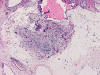

The excised specimen consists of multiple fragments of tan, soft tissue, 5.0 x 2.0 x 1.0 cm in aggregate, for examination. On gross examination, neither calcified tissue nor hair were found. An intraoperative frozen section and cytologic preparation was performed which revealed mature intestinal element, skin and small amount of hair. No germinoma element, yolk sac tumor (endodermal sinus tumor) element, embryonal cell carcinoma, or immature teratoma component was present in multiple specimens submitted for frozen section. Although a minute amount of hair was revealed on the frozen section, gross examination of the submitted tissue does not identify any hair or calcified tissue. An intraoperative diagnosis of teratoma with only mature element present was made.

The entire specimen was submitted for histologic examination. The bulk (over 99%) of the tumor was composed predominantly of mature intestinal elements (Panel A, B, and C) and skin, respiratory type mucosa, cartilage, and small amount of mature neural parenchymal tissue of the central nervous system (Panel D and E). Neither immature nor malignant elements are present. Small microscopic foci of well demarcated, neural parenchymal tissue with increased atypia (arrow in panel F) are noted. On higher magnification (Panel G and H), these areas contain large, bizarre appearing cells with dark chromatin but no prominent nucleoli. There are also scant multinucleated cells and mineralized substances (arrow in Panel H). Another example of these foci is illustrated in Panel I, J, and K. These atypical foci comprised less than 1% of the volume of the tumor. They are all microscopic in size and show no evidence of expansion or invasion into the surrounding tissue.